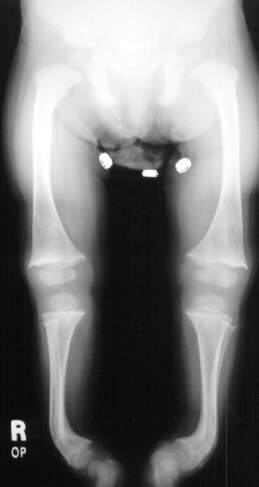

You

would plan to do tibial osteotomies to correct the severe varus

deformities in approximately 1 year after a good response the

nutritional management is seen.

On

further testing the child was found to have elevated serum, BUN

and creatinine. It is now likely that all these changes are due

to chronic renal failure.

Rickets

always causes knee varus deformities.